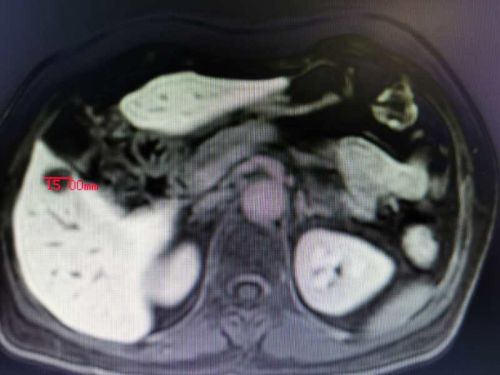

通过多项检查诊断技术全面评估肿瘤部位及患者全身状况, CT及MRI(普美显)提示患者乙状结肠癌并肝脏寡转移瘤,结直肠肛门外科、肝胆外科、放射科、肿瘤科、病理科开展晚期结直肠癌MDT讨论认为,患者乙状结肠癌肝转移合并不完全性肠梗阻,暂不适合术前新辅助化疗,有乙状结肠癌和肝转移瘤同时R0切除手术机会,但同时切除手术难度及风险增加。

肝转移瘤